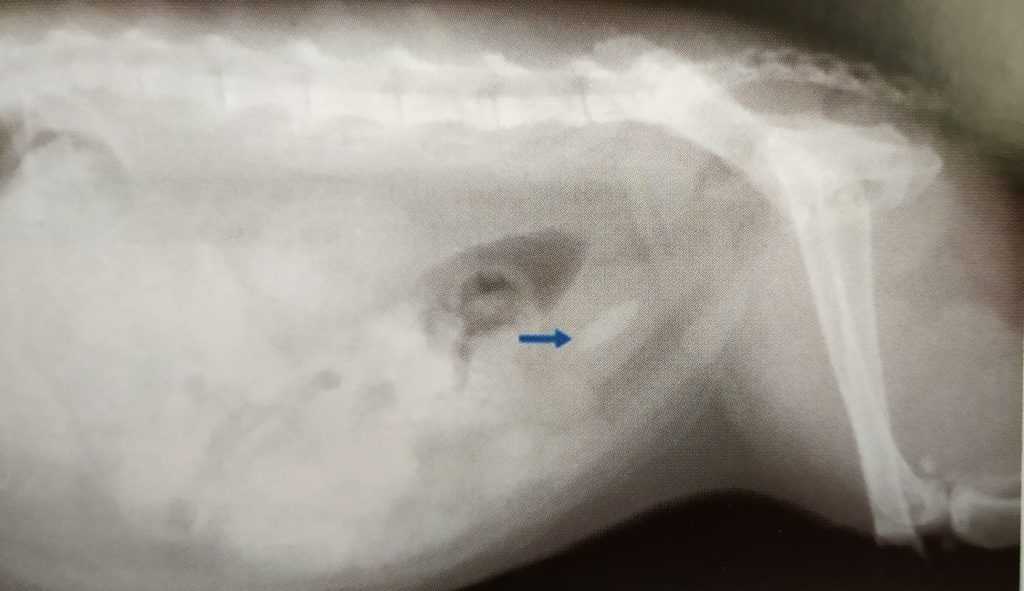

Рентген брюшной полости, стрелкой показан крупный одиночный уролит